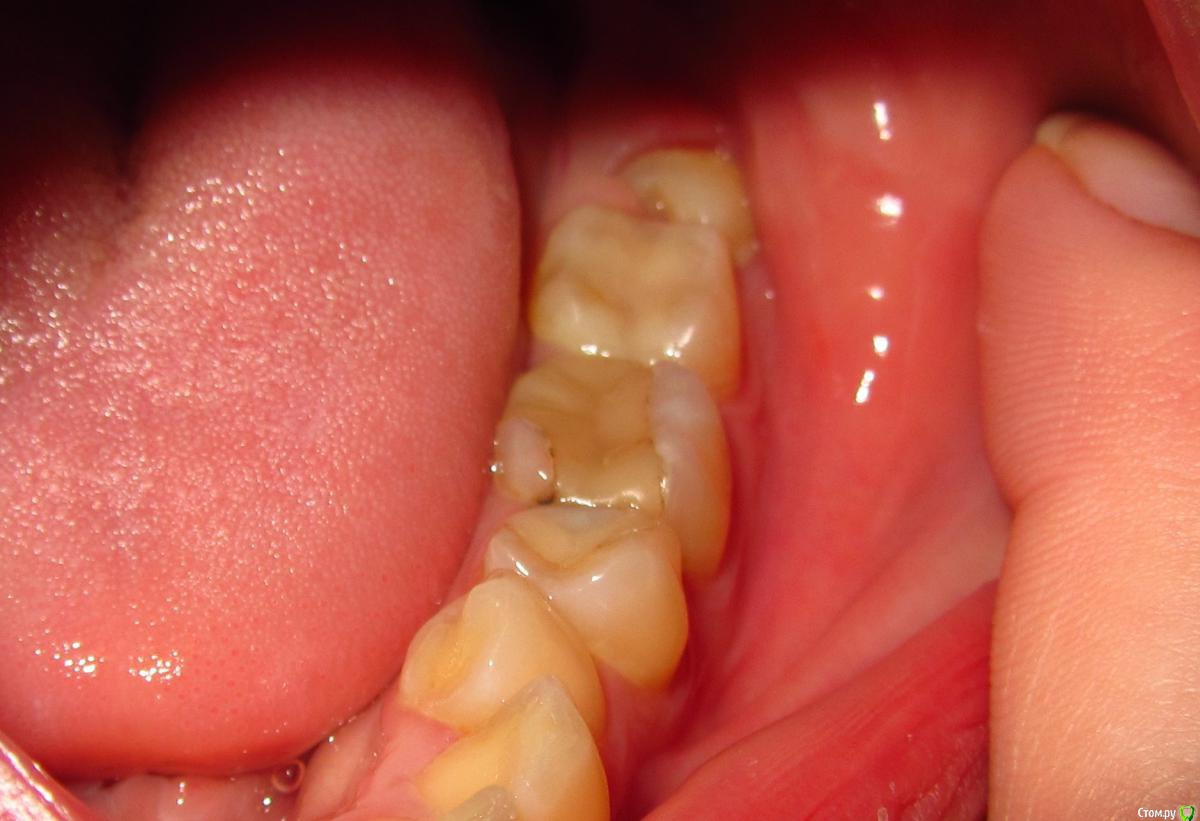

aqua1 Опубликовано 8 февраля, 2015 Поделиться Опубликовано 8 февраля, 2015 Добрый день! История моя давняя и до сих пор не решена….Где-то в 2007 году удалили в нижней 5-ке нерв, но зуб иногда «простреливал» при случайном накусывании по ночам. Подозреваю, что неудачное лечение могло быть связано с тем, что немного передержали лекарство, так как врач был в отпуске..Через полгода, в 2008 году на десне между 5 и 6 образовался бугорок, снимок показал воспаление на корне. Так как каналы на снимке были запломбированы хорошо, сказали что нет смысла их перелечивать, и зуб придётся удалить(( Естественно, меня такой поворот не устраивал, зуб был хорошо сохранен, никогда не беспокоил, и лечение кариеса изначально было просто профилактическим, но канал оказался слишком близко... Второй вариант был антибиотики, образовался свищ, а вскоре всё зажило и припухлость полностью спала (хотя на снимке 2009 года ситуация не изменилась).Ни зуб, ни дёсны не беспокоили меня абсолютно до весны 2012 года, когда после ветреной погоды, зуб поныл 2 дня и образовалась даже не припухлость, а затвердевшая дуга вдоль 6-8 зубов. Боли и воспаления не было. Испугавшись, что это будет расти и дальше такими же темпами, поехала в стоматологию, где терапевт отправила меня к хирургу, у которого было 2 варианта – резать или вырывать. На новом снимке никаких изменений опять замечено не было.. Десну разрезали между 5 и 6, гноя не было, потом отёк сошёл, а затвердение нет.В настоящий момент оно особо не беспокоит, только иногда ощущается в челюсти, асимметрии лица тоже вроде не заметно. В 2014 году начала активно лезть полулежачая восьмерка, без боли и воспаления. Затвердевшая дуга на десне начинается под 6-м зубом и плавно уходит за эту 8-ку. По случаю всего этого в январе 2015 сделали панорамный снимок всей этой красоты.Очень нужны ваши советы!1) Обязательно ли удалять эту 5-ку или как её лечить? Сойдет ли затвердение на десне после удаления? Что это вообще может быть?2) Я так понимаю, что 8-ка на удаление. Стоит ли немного подождать, пока она вылезет побольше, чтобы легче её удалить?Заранее спасибо. Прилагаю всю историю в рентгенах, а также фото, как это выглядит сейчас вживую. Ссылка на комментарий

aqua1 Опубликовано 8 февраля, 2015 Автор Поделиться Опубликовано 8 февраля, 2015 (изменено) Разъяснения по снимкам:1) весна 2008 года - начало2) 2009 год3) весна 2012 года - сразу после обострения и появления отвердевшей десны4) свежий снимок 2015 года5) так выглядит зуб мудрости4) зубы и десна в обычном состоянии7) и 8) - изображения отвердевшей дуги на десне вдоль 6, 7 и 8 зубов (т.е. та область, что между зубами и пальцем) Изменено 8 февраля, 2015 пользователем aqua1 Ссылка на комментарий